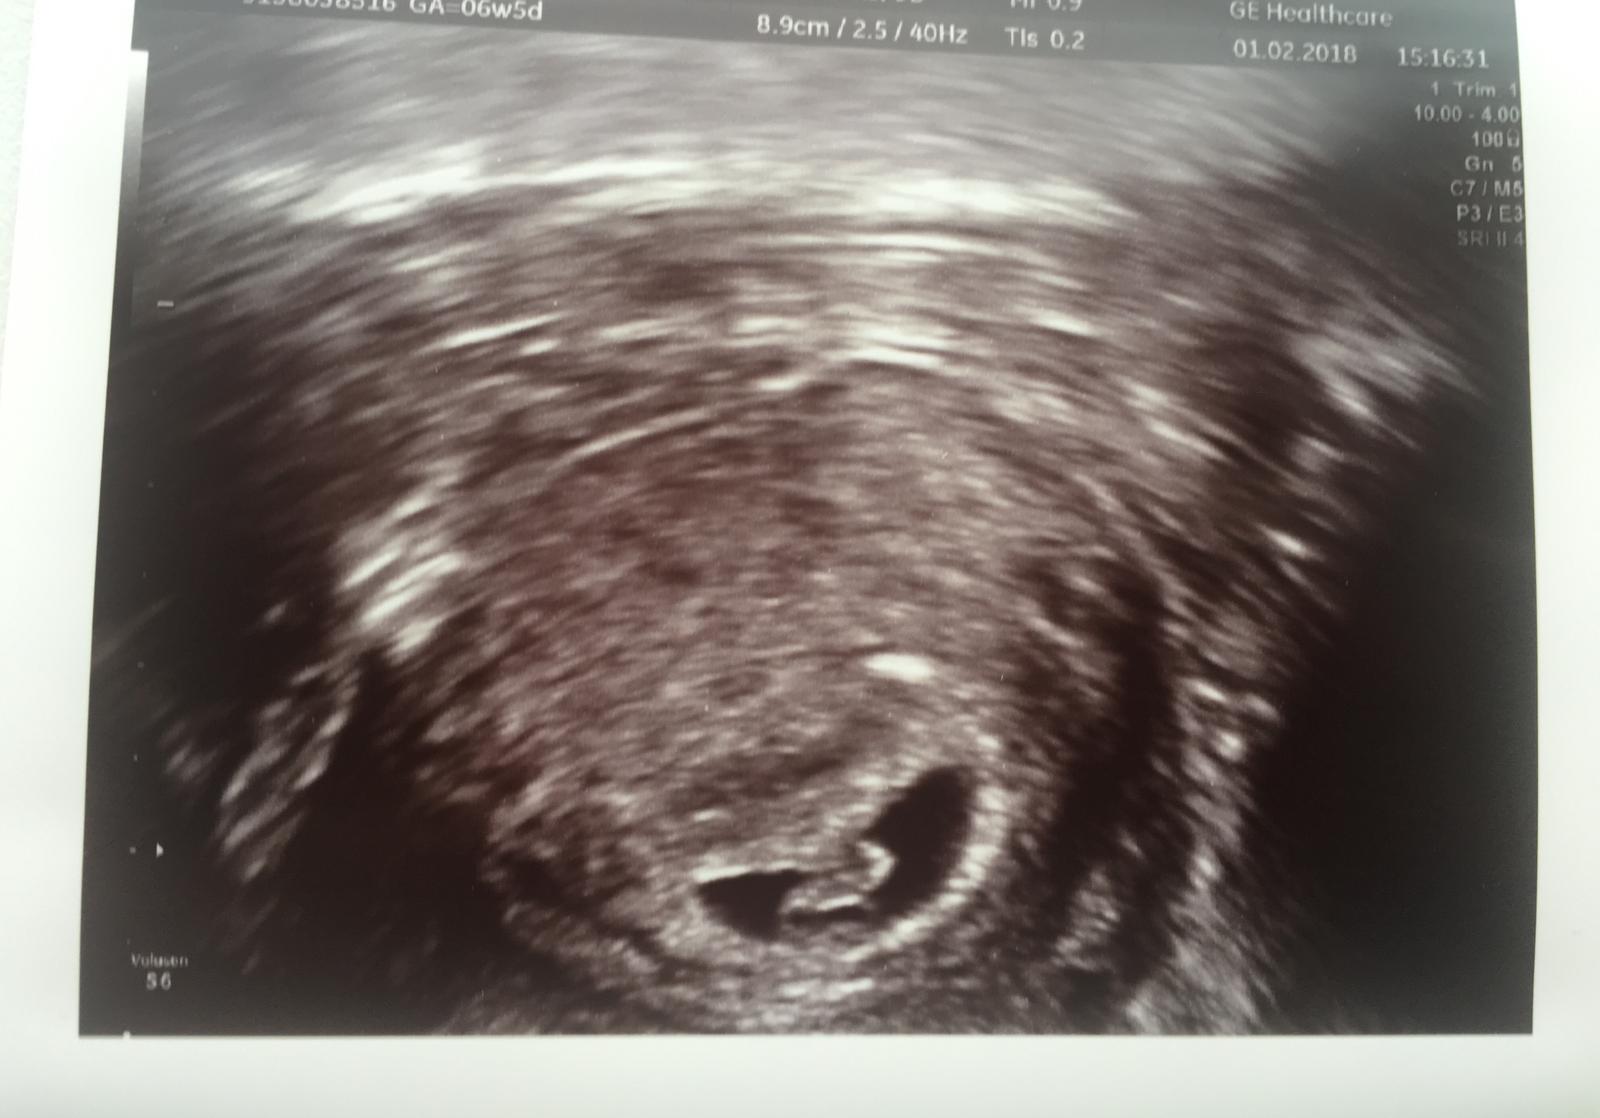

Ahojte baby, ked si pamatate asi pred 2 tyzdnami som sem pridavala testy, 2 som mala celkom viditelne a potom na dalsi den mi uplne zoslabol (dalsi den zase v poriadku). Vtedy v den toho slabeho testu mi vela ludi hovorilo, ze to bude asi biochemko. Len Vas chcem povzbudit, aby ste tolko tie testy nesledovali, ja som sa tiez nastrasila a dnes uz nasa fazulka vyzera takto. 😊